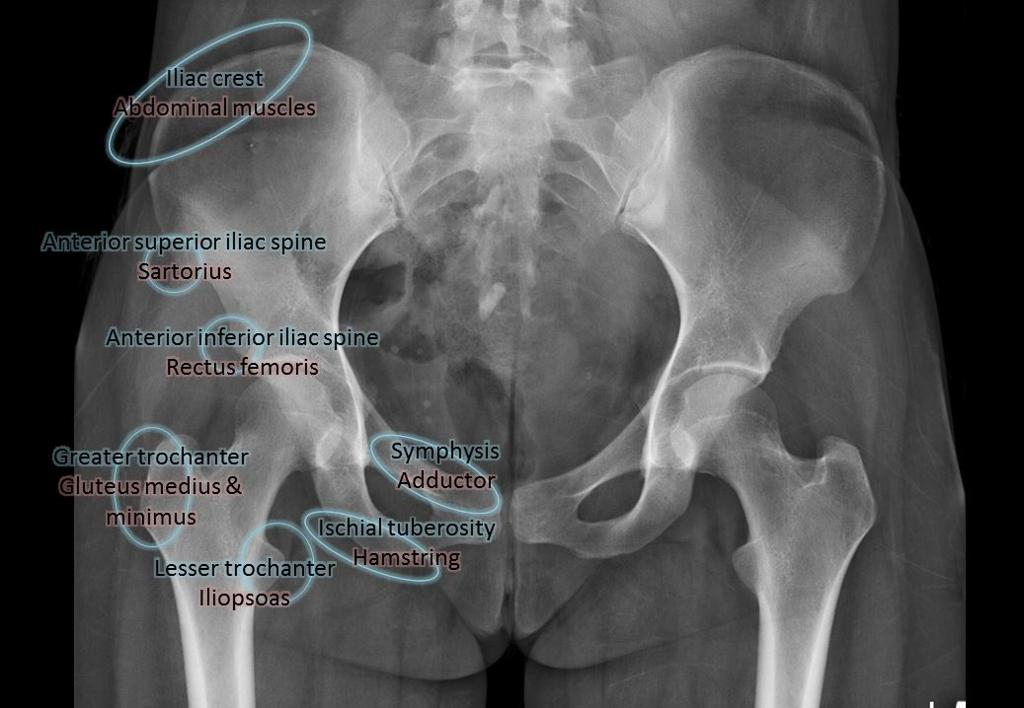

Avulsion of bone fragments is not uncommon in children with open cartilage at sites of tendon attachment. There are multiple sites around the hip that sustain these injuries, and they are more commonly associated with stiff hips and hip impingement. Muscles are tighter on the side of hip impingement. The need for surgical treatment for fractures displaced more than 10 mm is controversial.

Avulsion Fracture Sites

| Site | Muscle / Cause | Notes |

|---|---|---|

| AIIS | Straight head of rectus femoris; soccer/football | Heals quickly; can leave bony prominence causing subspine impingement. No indication for acute repair. |

| ASIS | Sartorius; forced flexion | Pain resolves quickly; resume activities as tolerated. |

| Iliac crest | Abdominal muscles | Heals well with early mobilisation. |

| Pubic tubercle | Adductor longus and pectineus | Heals well with activity modification. |

| Pubic symphysis | Rectus abdominis | Usually treated non-operatively with early mobilisation. |

| Ischial tuberosity | Proximal hamstring tendons | Complete ruptures cause chronic pain and weakness. Surgical repair has better outcomes but more complications. |

| Greater trochanter | Direct trauma; hip abductors | High risk of AVN in children. Displacement >5 mm is better treated surgically. |

| Lesser trochanter | Iliopsoas tendon | May cause LT or ischiofemoral impingement. Late excision or distal transfer for persistent pain. |